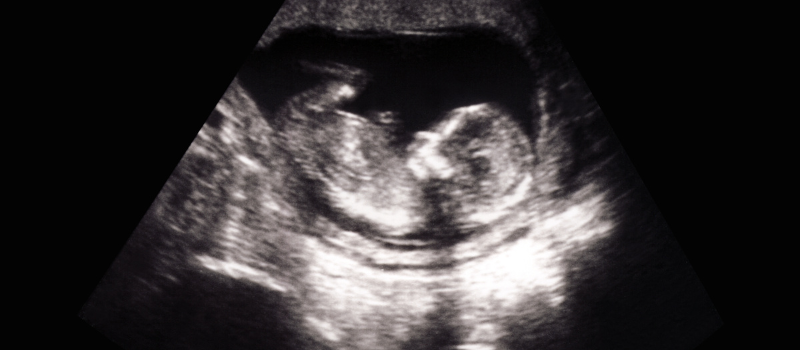

Babies may appear to breathe in the womb, but they’re really practicing breathing. In utero, babies are swimming in amniotic fluid and getting oxygen from mom. “This practice breathing shows us that babies are doing well inside the uterus, as those who aren’t won’t extend this extra effort,” said Tina Hendrick, M.D., a board-certified OBGYN and medical director at OB Hospitalists of Kentucky, part of Pediatrix® Medical Group. As the lungs develop, they can be seen expanding and contracting on ultrasound. A related phenomenon is crying in the womb, which Dr. Hendrick said there is evidence of. Grimacing, chin quivering and open mouths can all be observed on ultrasound.